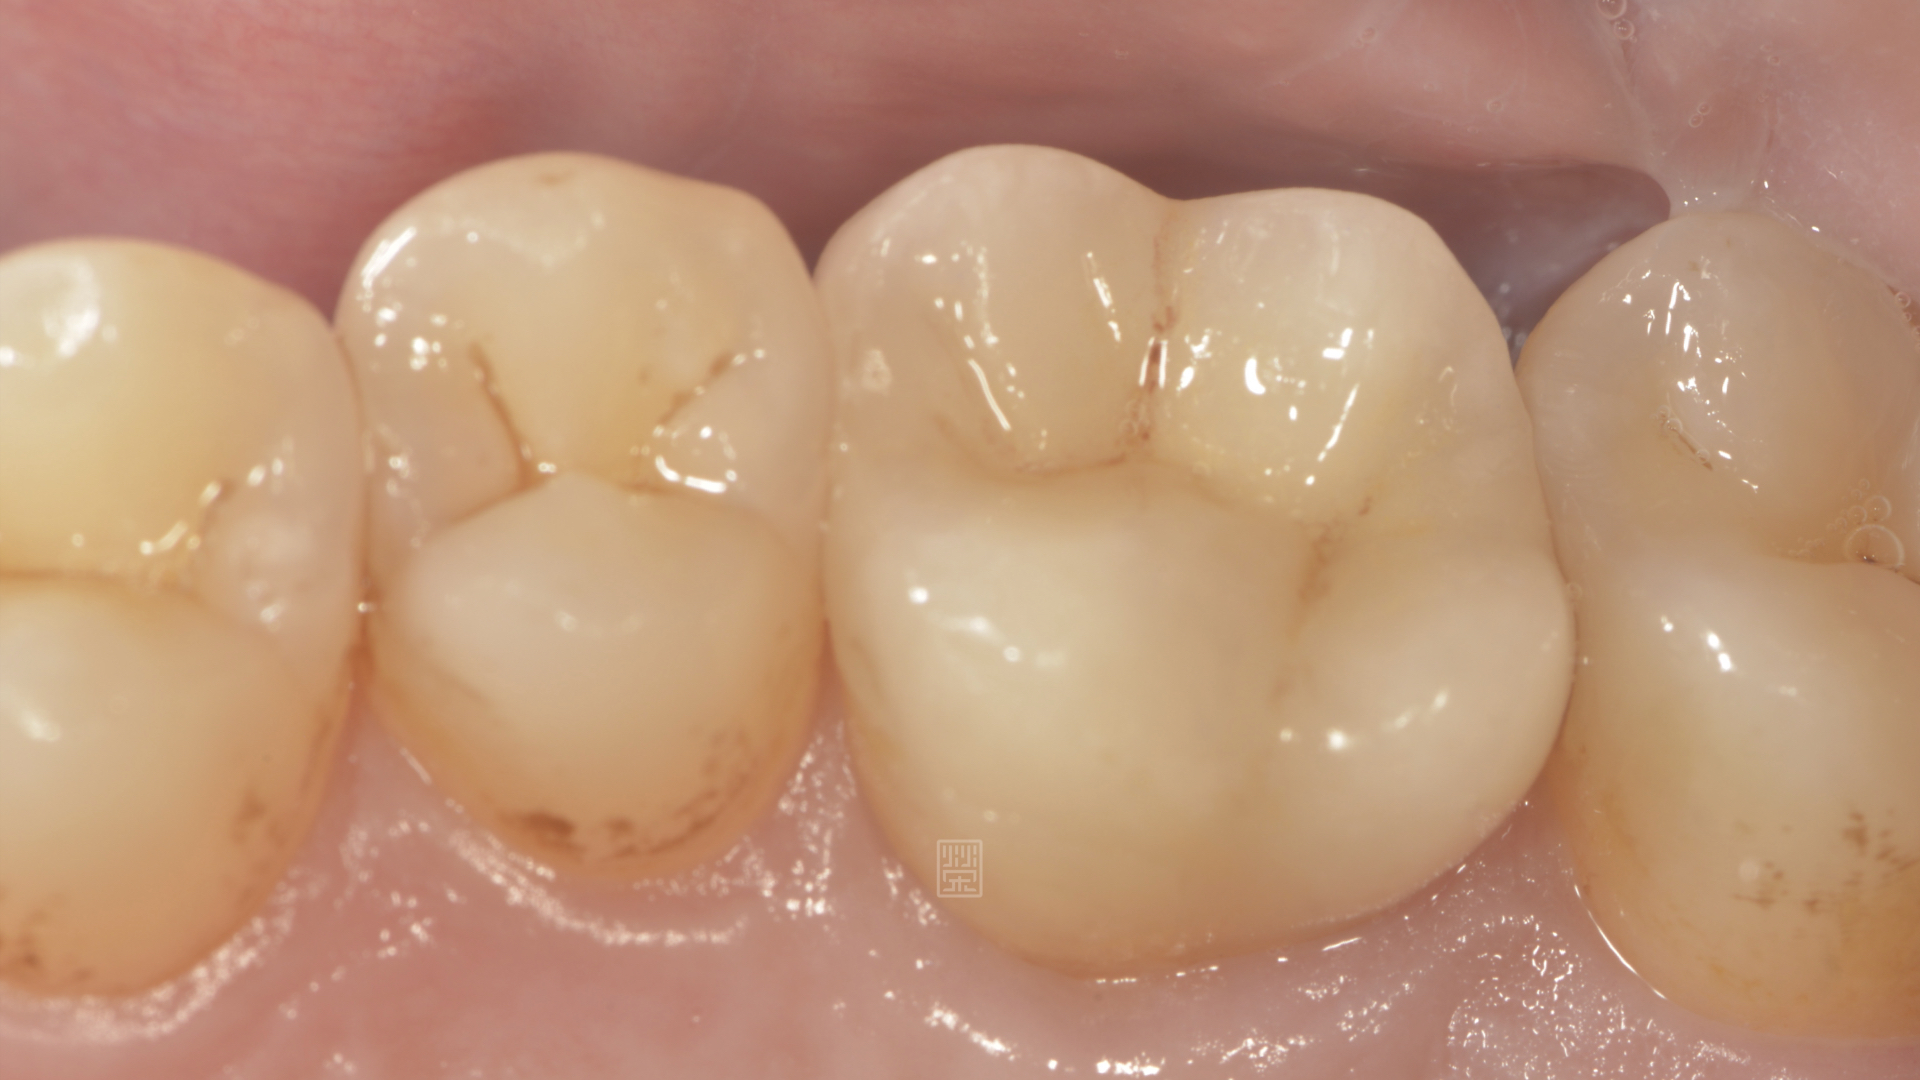

全瓷嵌體完成